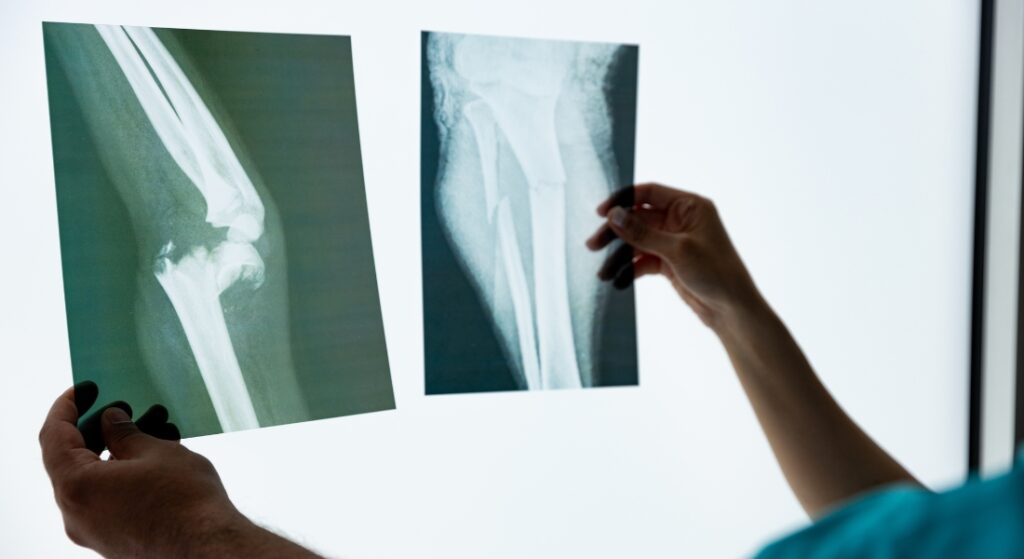

Chụp X-quang xương khớp

- Chẩn đoán gãy xương, trật khớp (cổ tay, cổ chân, vai, đùi, cột sống).

- Phát hiện các bệnh mạn tính: loãng xương (hình ảnh xương mờ, mất vỏ xương), thoái hóa khớp (hẹp khe khớp, gai xương).

- Đánh giá sau phẫu thuật kết hợp xương, theo dõi tiến triển xương liền hay không.